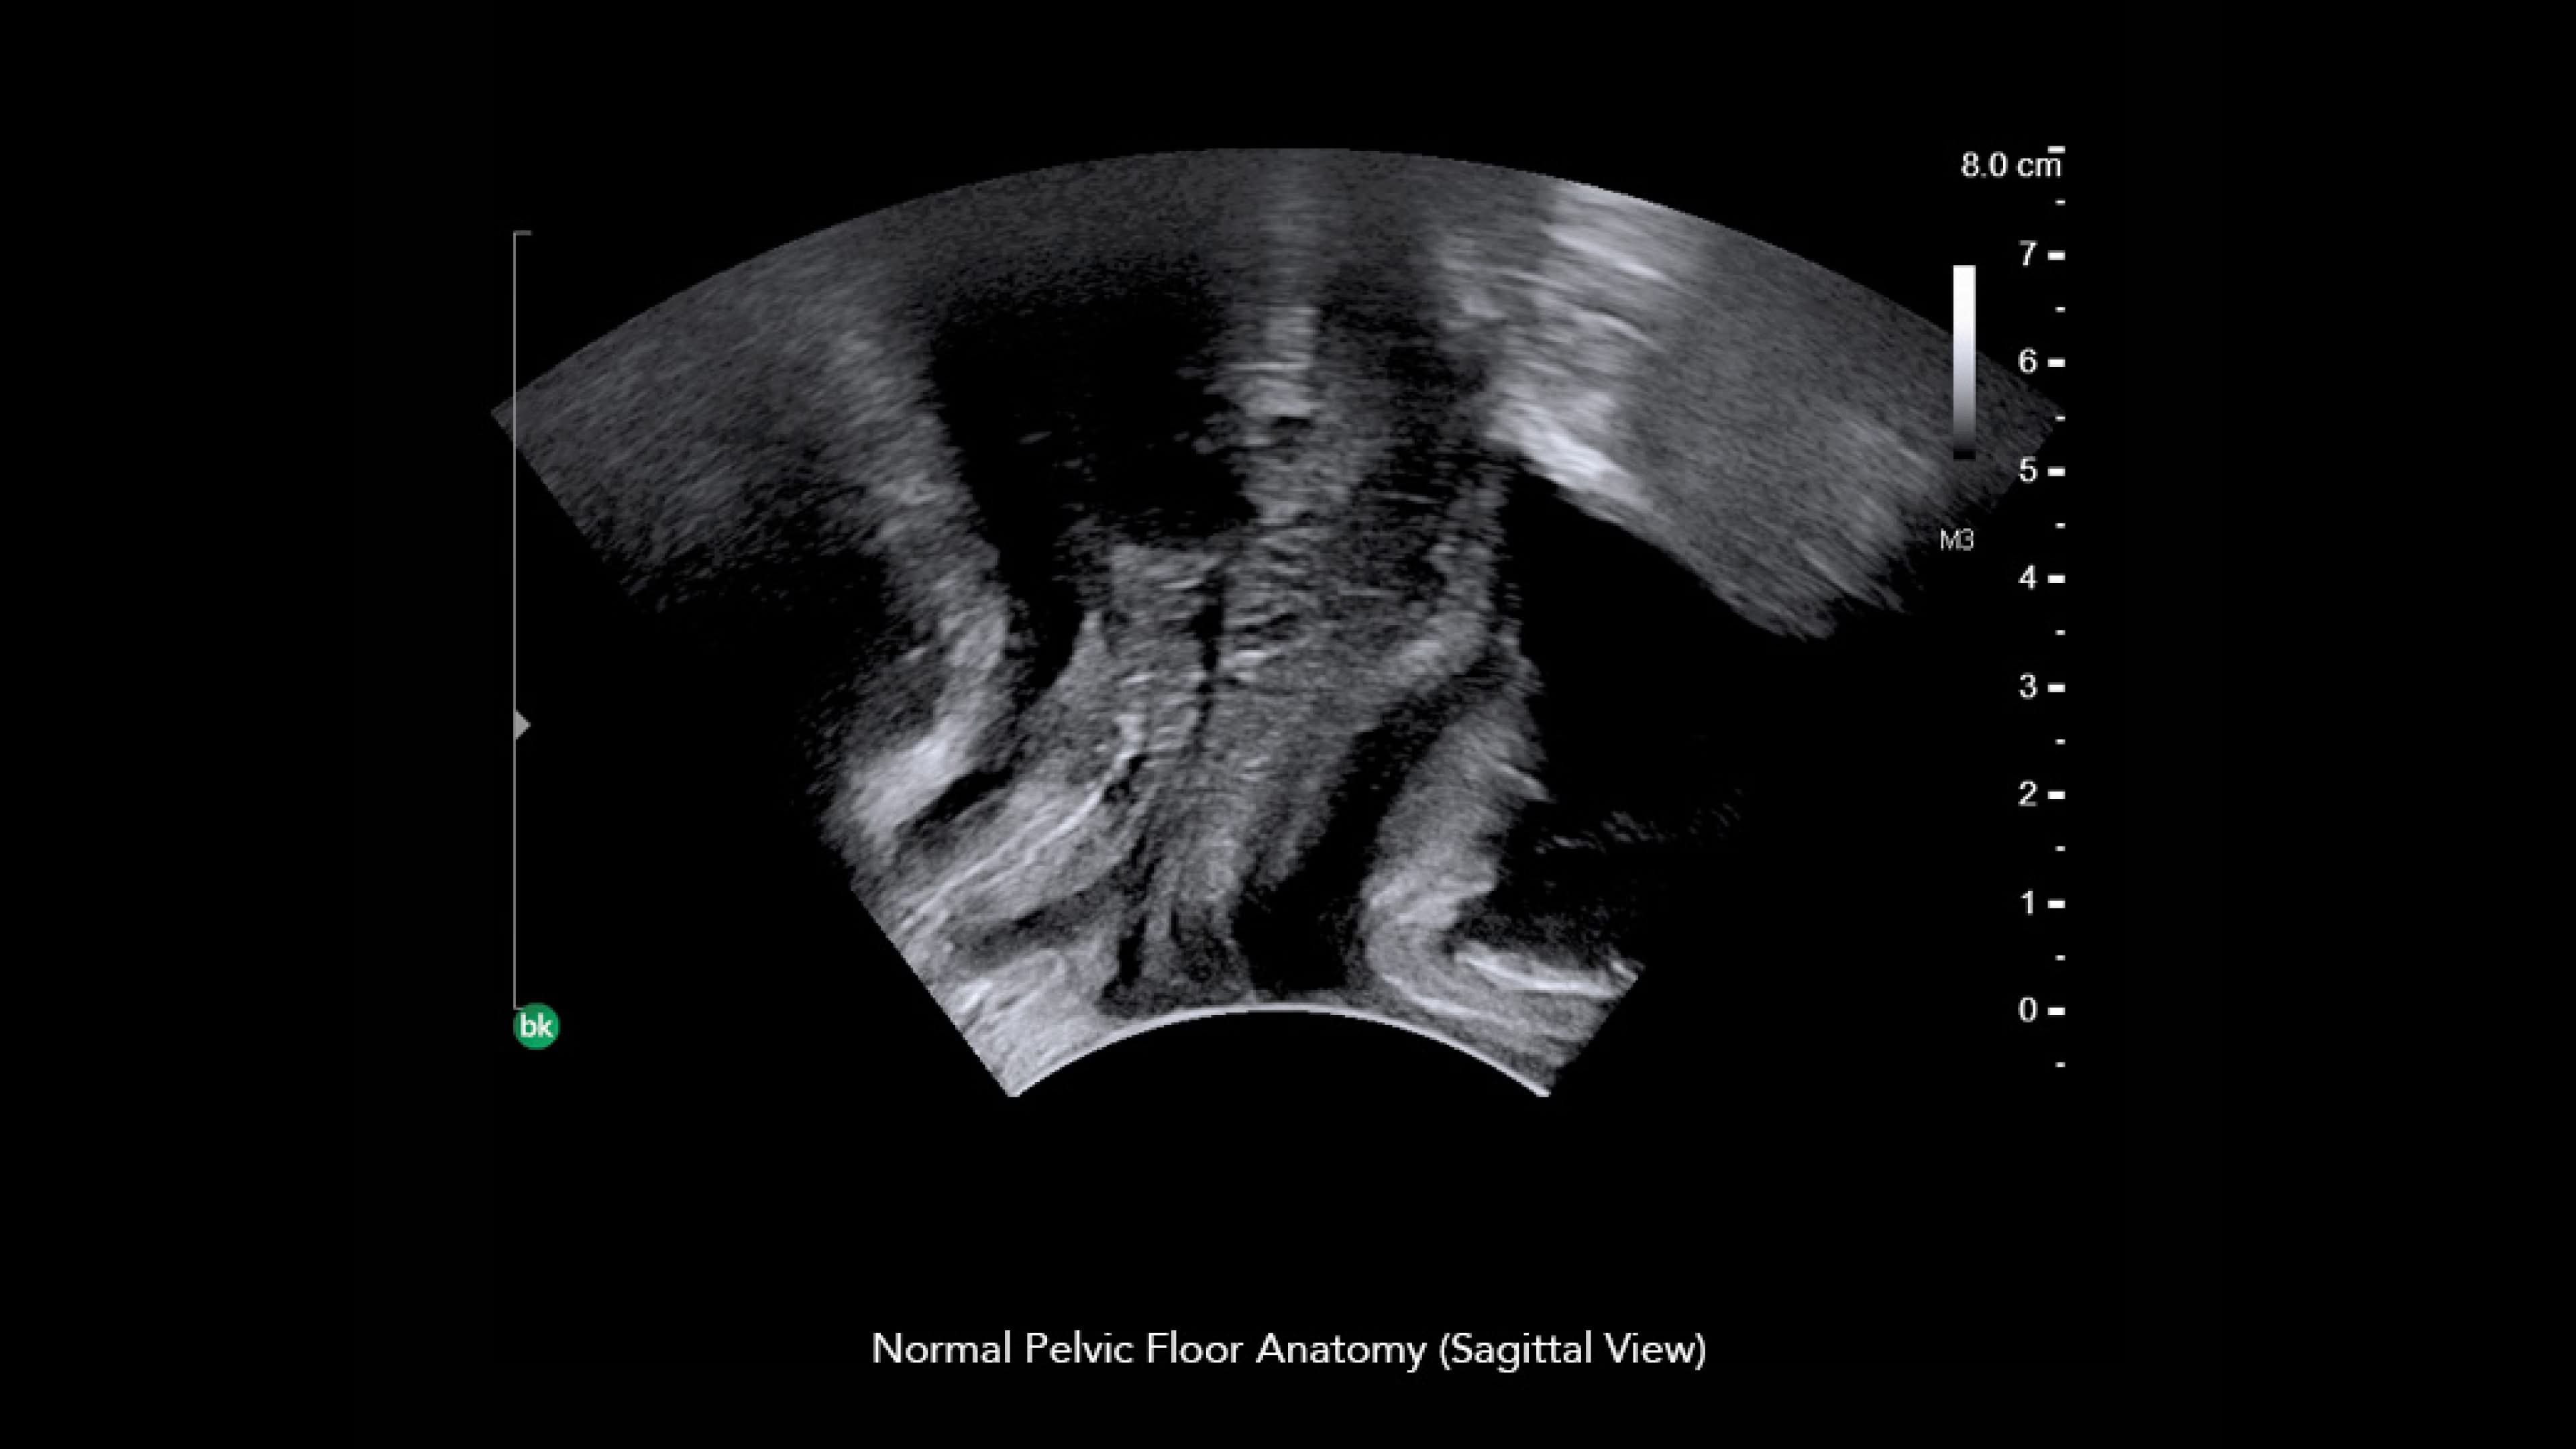

Discover the bkActiv ultrasound system for enhanced visualization and precision in general surgery, neurosurgery, urology, colorectal, and pelvic floor procedures.